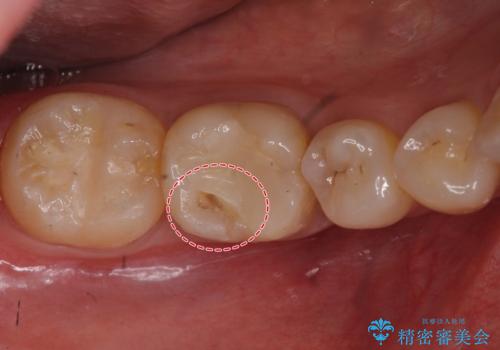

下の奥歯は口を開くと簡単に外から見えてしまいます。

銀色だった歯が白くなったことで大変喜んでいただけました。

- 右下6 仮歯+セラミッククラウン 11000円+110000円費用は治療当時の料金となります